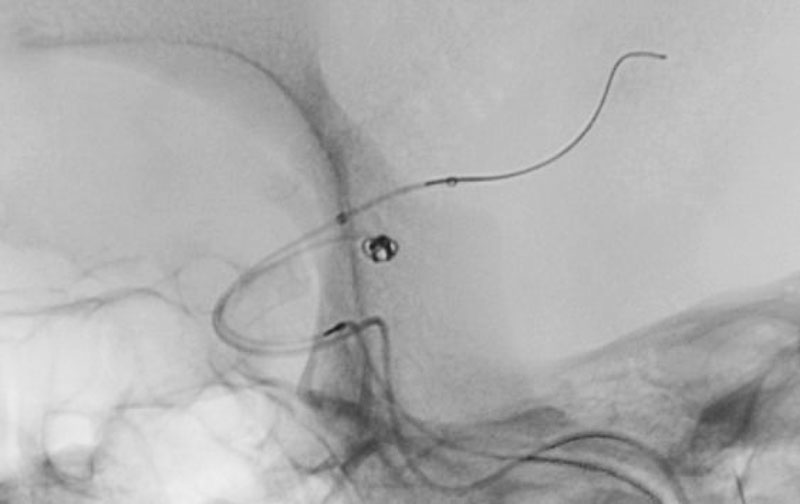

'26年4月

左後下小脳動脈瘤

80代

大阪府の病院

No.1631 手術中